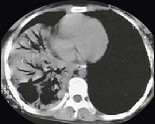

- 单项选择题女,24岁, 咳嗽咳痰伴高热3天,如图所示, 最可能的诊断为 ( )

A、右下肺干酪性肺炎

B、右下肺大叶性肺炎

C、右中肺大叶性肺炎

D、右中叶肺脓肿

E、右下肺不张